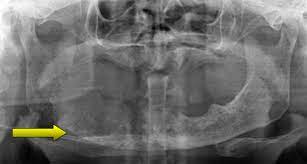

Blockage can lead to kidney damage, kidney stones, and infection. Warmth around incision or knee. Managing side effects (general information) How is liver cancer diagnosed? Learn more about receding gums in this article. Symptoms can include pain in the side, decreased or increased urine flow. See a doctor if you have dirty white, greenish, or black discharge from your nipple. Symptoms of scleritis include pain, redness, tearing, light sensitivity (photophobia), tenderness of the eye, and decreased visual acuity. Eat foods rich in antioxidants such ad spinach, carrots, green leafy vegetables, beat roots, raspberries, etc. Symptoms include jaw pain or numbness, red or swollen gums, loose teeth, or slow healing after dental work. Locking of the joint, making it difficult to open or close your mouth. Once the gums recede, they cannot grow back. The symptoms of inadequate ventilation are:

Ventilation could result in death. The pain may be boring, stabbing, and often awakens the patient from sleep.the extreme pain of scleritis helps to differentiate it from other common. Forced air means that a blower or fan pushes the air through the heater. This can cause damage to supporting bone. Warmth around incision or knee. Acute damage typically involve the mucosa of the mouth. Signs and symptoms of tmj disorders may include: Xgeva may cause bone loss (osteonecrosis) in the jaw. An odor is only detectable at close proximity to the patient and when the dressing is removed. Purple spots on the skin. Aching pain in and around your ear. They can help reduce swelling and bruising after surgery. How is liver cancer diagnosed?